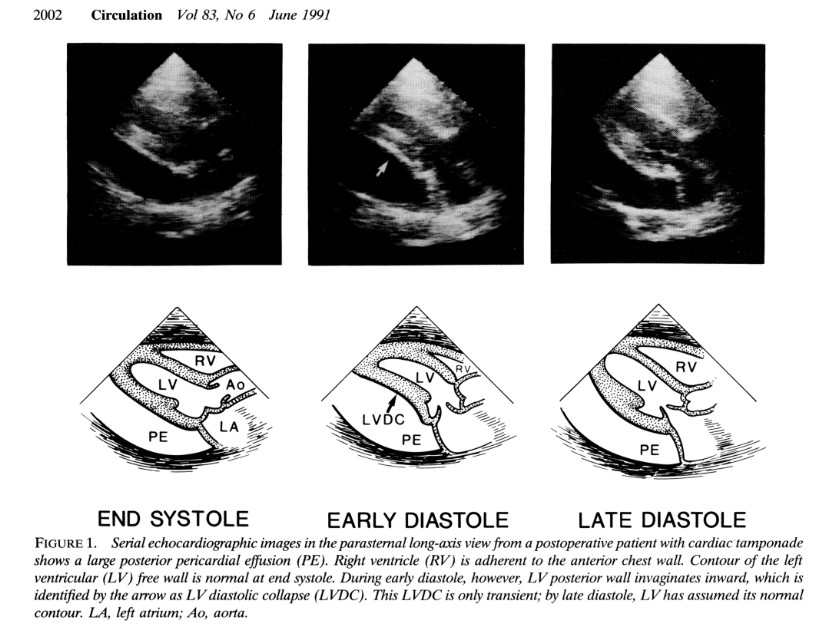

O colapso diastólico do VE foi descrito pela primeira vez por Chuttani et al., quando foi observado ser uma causa frequente de tamponamento após cirurgia cardíaca por presença de aderências entre as cavidades direitas do coração e a parede torácica, com tendência a uma localização mais posterior.